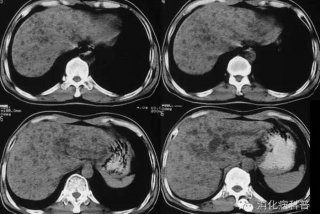

肝血吸虫病ct表现 肝血吸虫病ct影像学表现

肝血吸虫病ct表现 肝血吸虫病ct影像学表现,对于想了解百科知识的朋友们来说肝血吸虫病ct表现 肝血吸虫病ct影像学表现是一个非常想了解的问题,下面小编就带领大家看看这个问题。一、引言 肝血吸虫病是一种由血吸虫寄生在肝脏中引发的疾病。随着医学影像学的发展,CT已成为诊断肝血吸虫病的...